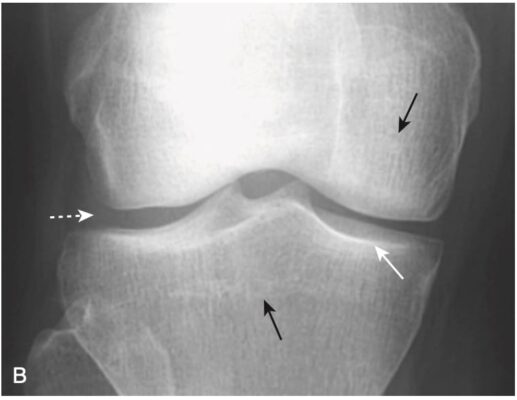

Hình 9. Bệnh khớp Charcot ở khớp gối do bệnh tiểu đường. Dấu hiệu đặc trưng của khớp Charcot là sự phân mảnh của xương xung quanh khớp, tạo ra nhiều mảnh xương nhỏ trong bao khớp (mũi tên trắng) và phá hủy khe khớp (mũi tên đen).